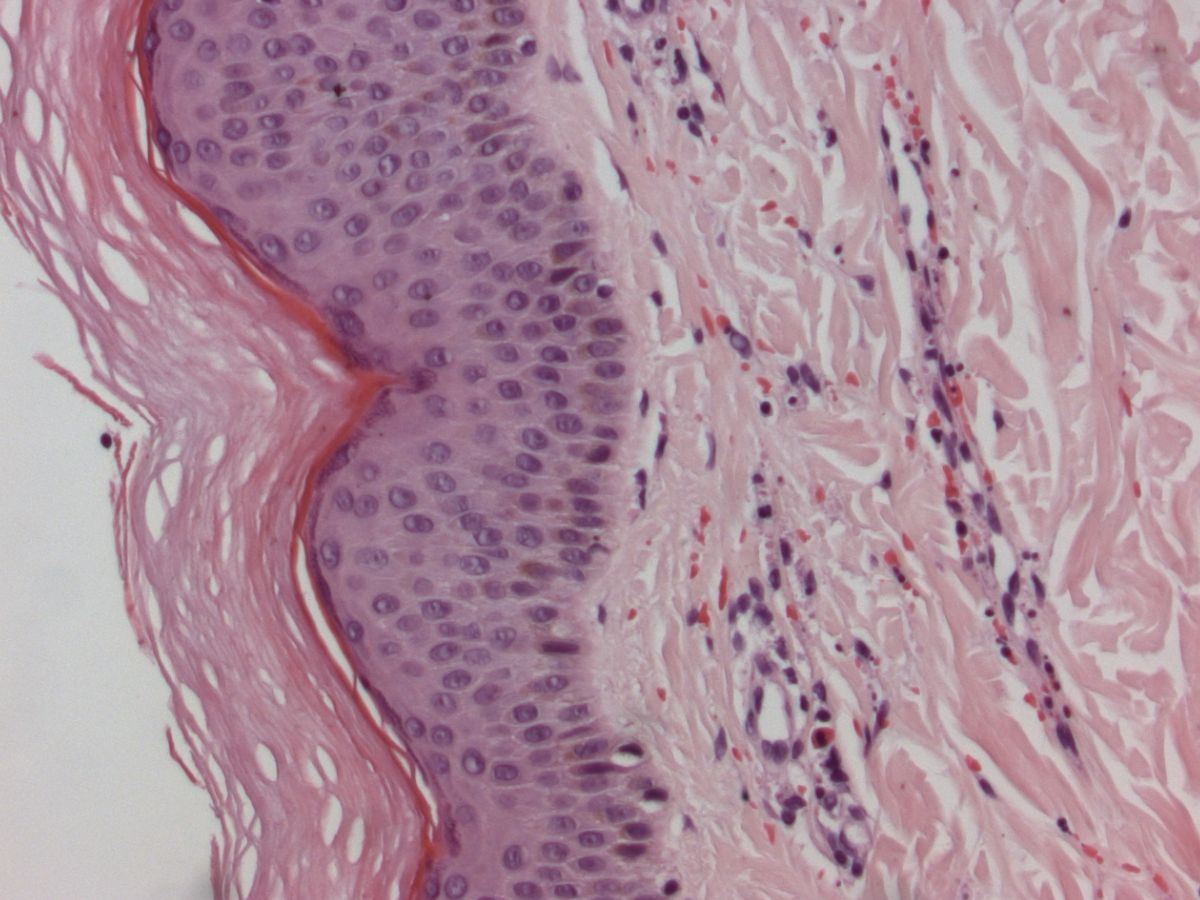

Histologie IgA vasculitis

ingescande coupe (zoom)

Bron hoge resolutie PA-foto: Kevin Kwee en Afdeling Pathologie MUMC. Klik op de afbeelding om in te zoomen.